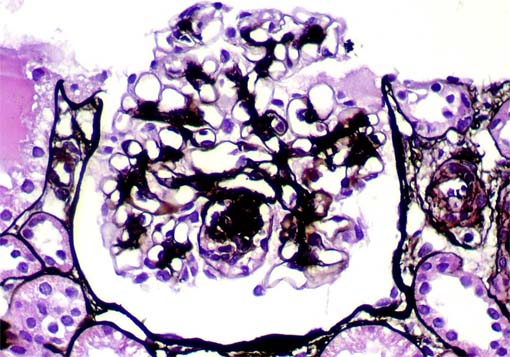

Figura 9.

Plata-metenamina, X400.